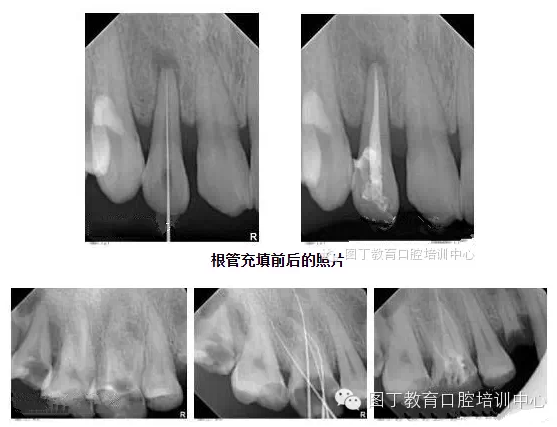

4、關(guān)于根管充填

總結(jié)幾個(gè)要點(diǎn):

1,根管充填到位的前提是根管要預(yù)備好;

2,把握好充填長(zhǎng)度;

3,選擇合適的主膠尖意義很大——合適的主尖其尖端恰好封閉根尖孔;

4,糊劑適量即可,因?yàn)槌涮畹闹黧w是牙膠。

5,側(cè)方加壓后的垂直加壓不可忽視,因?yàn)橥ㄟ^(guò)垂直加壓后的充填體更嚴(yán)實(shí)。

QQ圖片20150729094718.png